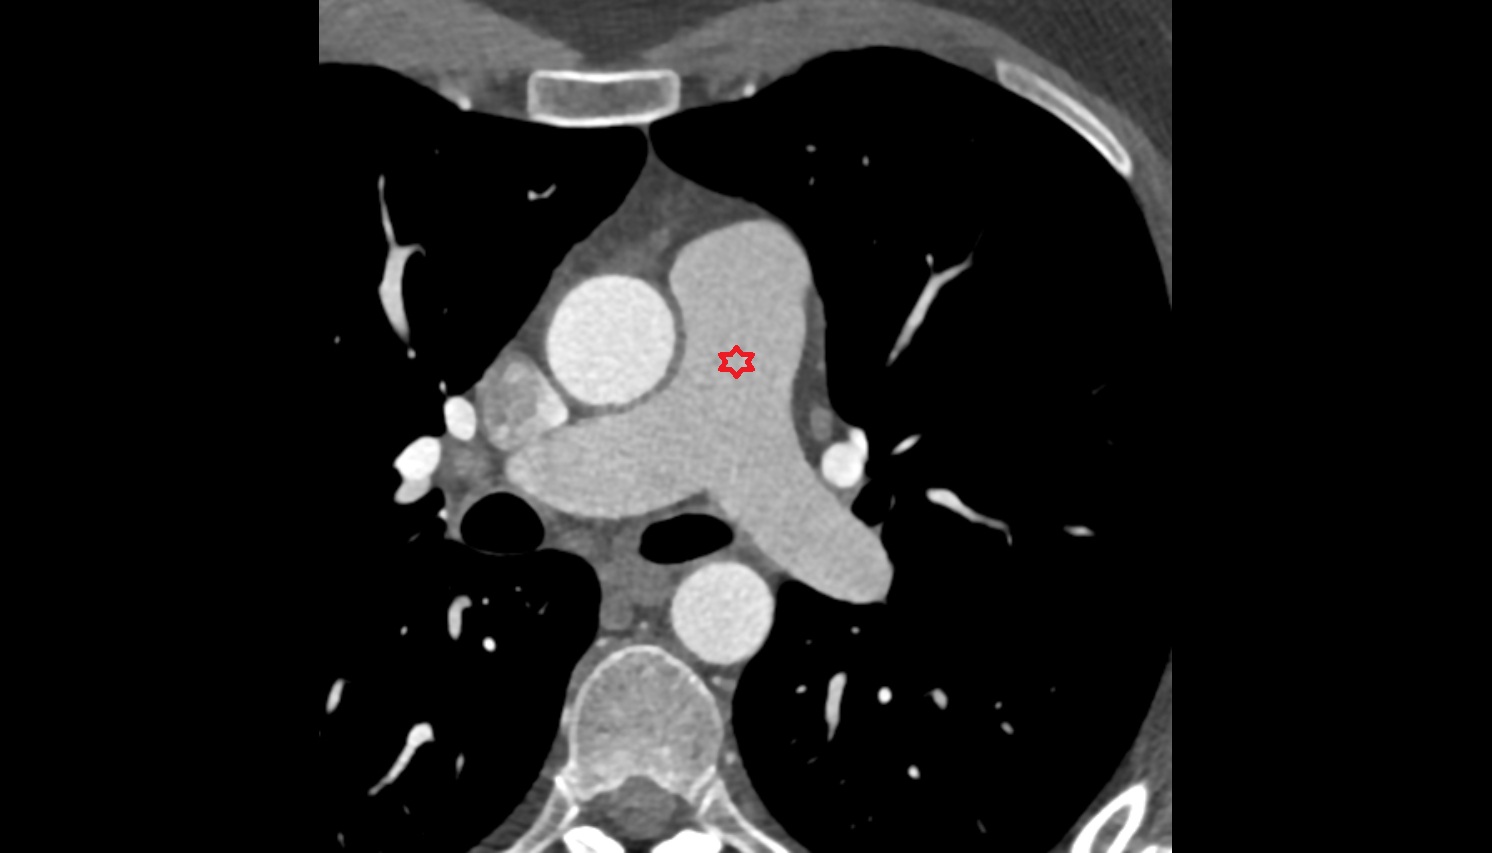

- Pericardium

- Heart

- Left atrium

- Pulmonary trunk

- Aortic root

- Ascending aorta